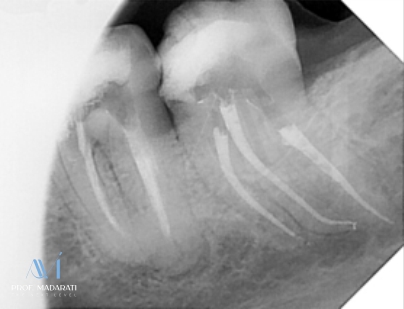

Obturation and Temporary Restoration:

Obturation was performed using the modified warm vertical compaction technique with Maaruchi bioceramic sealer.

A temporary restoration with Glass Ionomer Cement (GIC) was placed. The patient was referred back to the referring dentist for the final restoration.